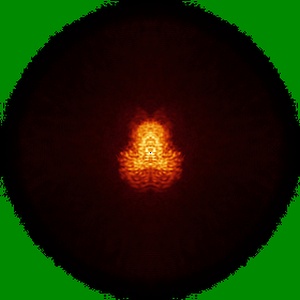

Cryo-EM structure of MPXV core protease in complex with aloxistatin(E64d)

Single-particle2.93 Å

Sample: PROTEASE DIMER